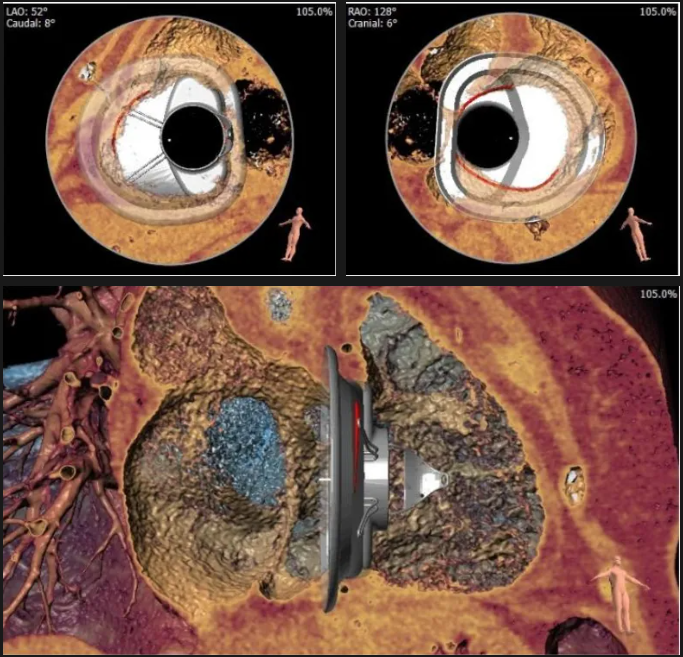

術(shù)前心臟CT評估

三尖瓣環(huán)平均周長徑54.3mm,最大直徑57mm

心房側(cè)周長平均徑(封堵高度)74.0mm

三尖瓣環(huán)切線位夾角 103°